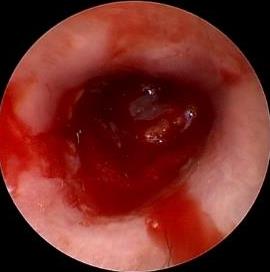

摘要:目的 探讨耳内镜下耳屏软骨-软骨膜鼓膜修补术后的短期疗效。方法 回顾性分析2019年9月-2022年8月该院收治的78例鼓膜穿孔患者的临床资料,患者均采用耳内镜下鼓膜修补术。术后随访3个月,观察鼓膜形态和穿孔愈合情况,记录内镜图像、干耳时间、术前术后听力及耳鸣情况,以及外耳道狭窄等并发症的发生率。结果 术后3个月,鼓膜穿孔愈合率为97.44%(76/78),愈合良好,平均气导听阈较术前明显改善,气骨导间距较术前明显缩小,耳鸣较术前明显改善,差异均有统计学意义(P<0.05)。干耳时间为(4.21±1.12)周。术后出现肉芽5例,再穿孔2例,真菌感染2例,术腔感染、耳屏感染、外耳道狭窄和切口瘢痕各1例,所有患者术后均未发生面神经麻痹和感音神经性聋等严重并发症。结论 耳内镜下耳屏软骨-软骨膜鼓膜修补术是一种安全、有效的手术方法。根据术后愈合规律、内镜下鼓膜和外耳道形态特征,可为鼓膜修补术后正常中耳转归和并发症的诊疗,提供临床参考。